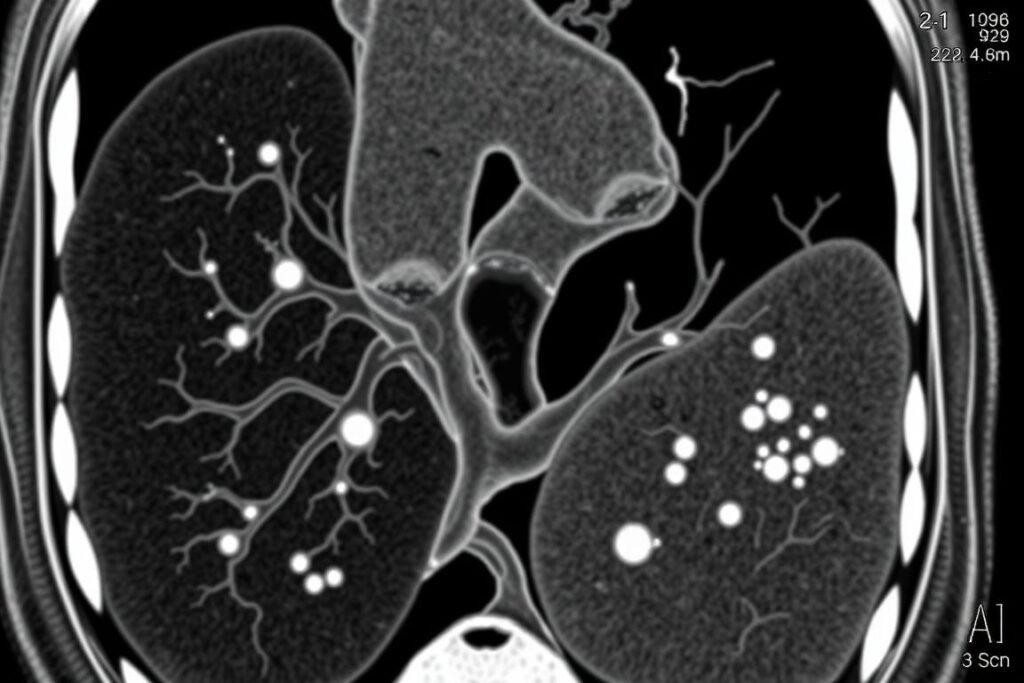

Cardiac CT scan showing calcium deposits (bright white areas) in coronary arteries

Coronary Artery Calcium (CAC) Score

This non-invasive CT scan measures the amount of calcium in your coronary arteries. Your doctor will calculate an Agatston score based on the quantity, density, and size of calcium deposits:

CAC Score | Interpretation | Risk Level |

0 | No identifiable plaque | Very low risk |

1-99 | Mild calcification | Mild to moderate risk |

100-399 | Moderate calcification | Moderate to high risk |

400+ | Severe calcification | High risk |